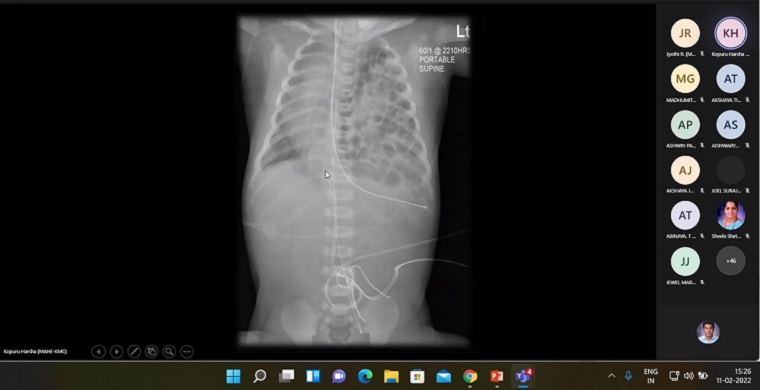

Department of Medical-Surgical Nursing, Manipal College of Nursing, Manipal organized a Guest Lecture on “Interpretation of Radiological Images” on February 11, 2022, between 2.30 pm & 4.30 pm to students of BSc Nursing, Nurse Practitioner in Critical Care (NPCC) residential program and MSc Nursing through Microsoft Teams Platform. Dr Kopuru Harsha, Senior Resident, Dept. of Radiology, KMC Manipal spoke on the topic. He emphasized on reviewing the basic anatomy of the thorax, lungs and head and elaborated on the basics of radiological images of chest x-ray, CT thorax and CT head. A total of 65 participants including BSc, MSc and NPCC students and faculty members of MCON participated in the session.